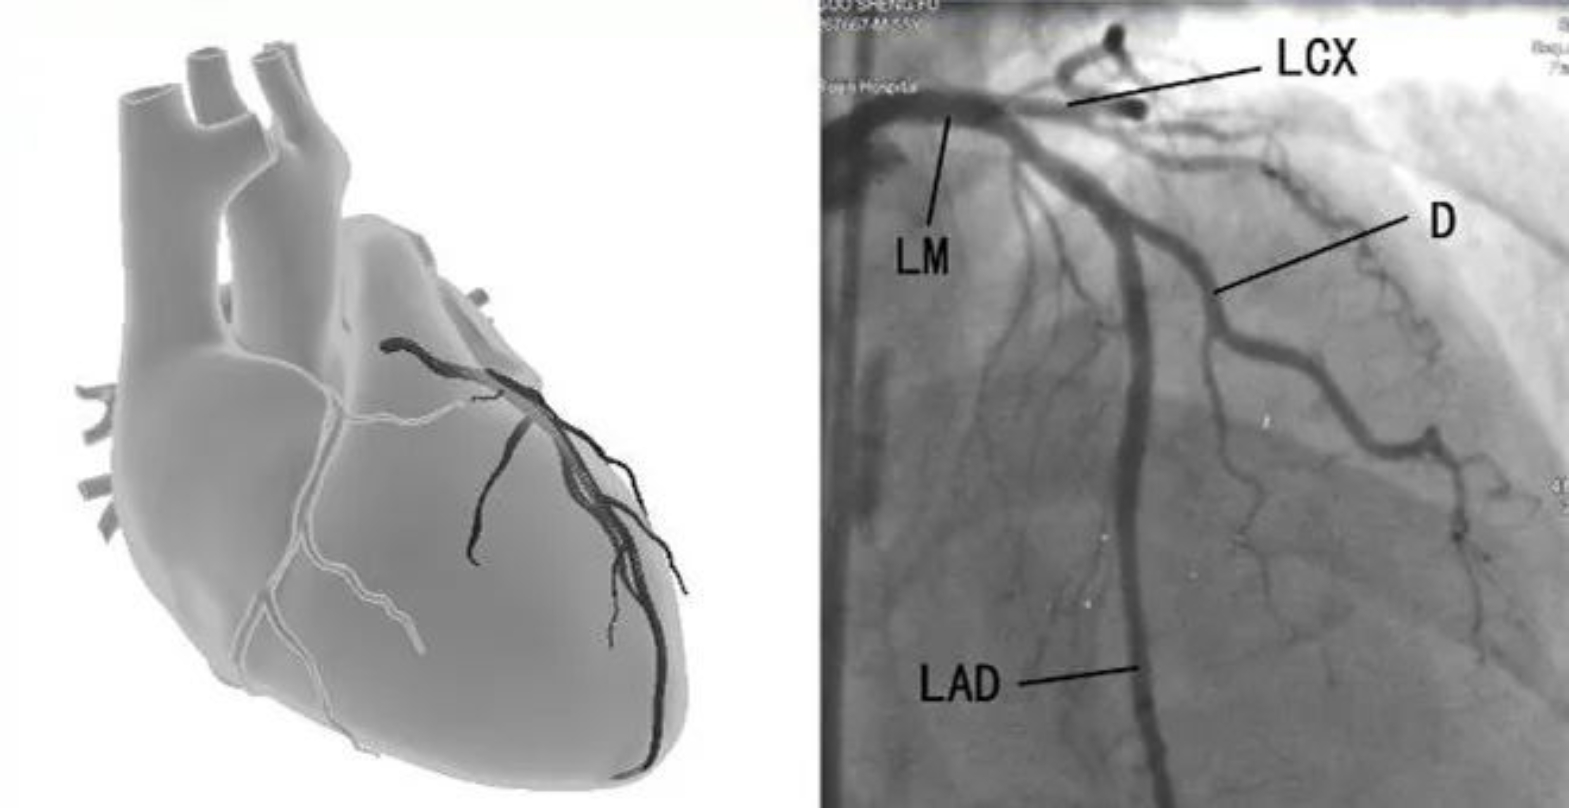

首先,千万不要仅凭借症状的轻重进行判断,一定要进行冠脉增强CT或者冠脉造影检查,因为冠心病这种疾病,症状的轻重程度和病情的严重程度很多情况下是不一致的。如果冠脉狭窄不严重,单纯的药物治疗就可以了。但是,如果是严重的冠脉狭窄,单纯的药物治疗就不够了,也可以简单理解为,严重的冠脉病变本身就不是药物治疗能解决的问题。像这种情况怎么办呢?

冠状动脉搭桥手术是广泛应用的有效而安全的治疗方法尽管很多人担心外科手术的创伤和风险,但是对于左主干病变和三支/多支冠脉病变,仍然是首选的推荐方案,尤其是合并糖尿病的患者,获益更大。那种认为冠脉搭桥手术是“最后的选择”甚至是“没有办法的办法”,而反复尝试不适合的方法或者一味的拖延等待,很可能会失去最佳的治疗效果。